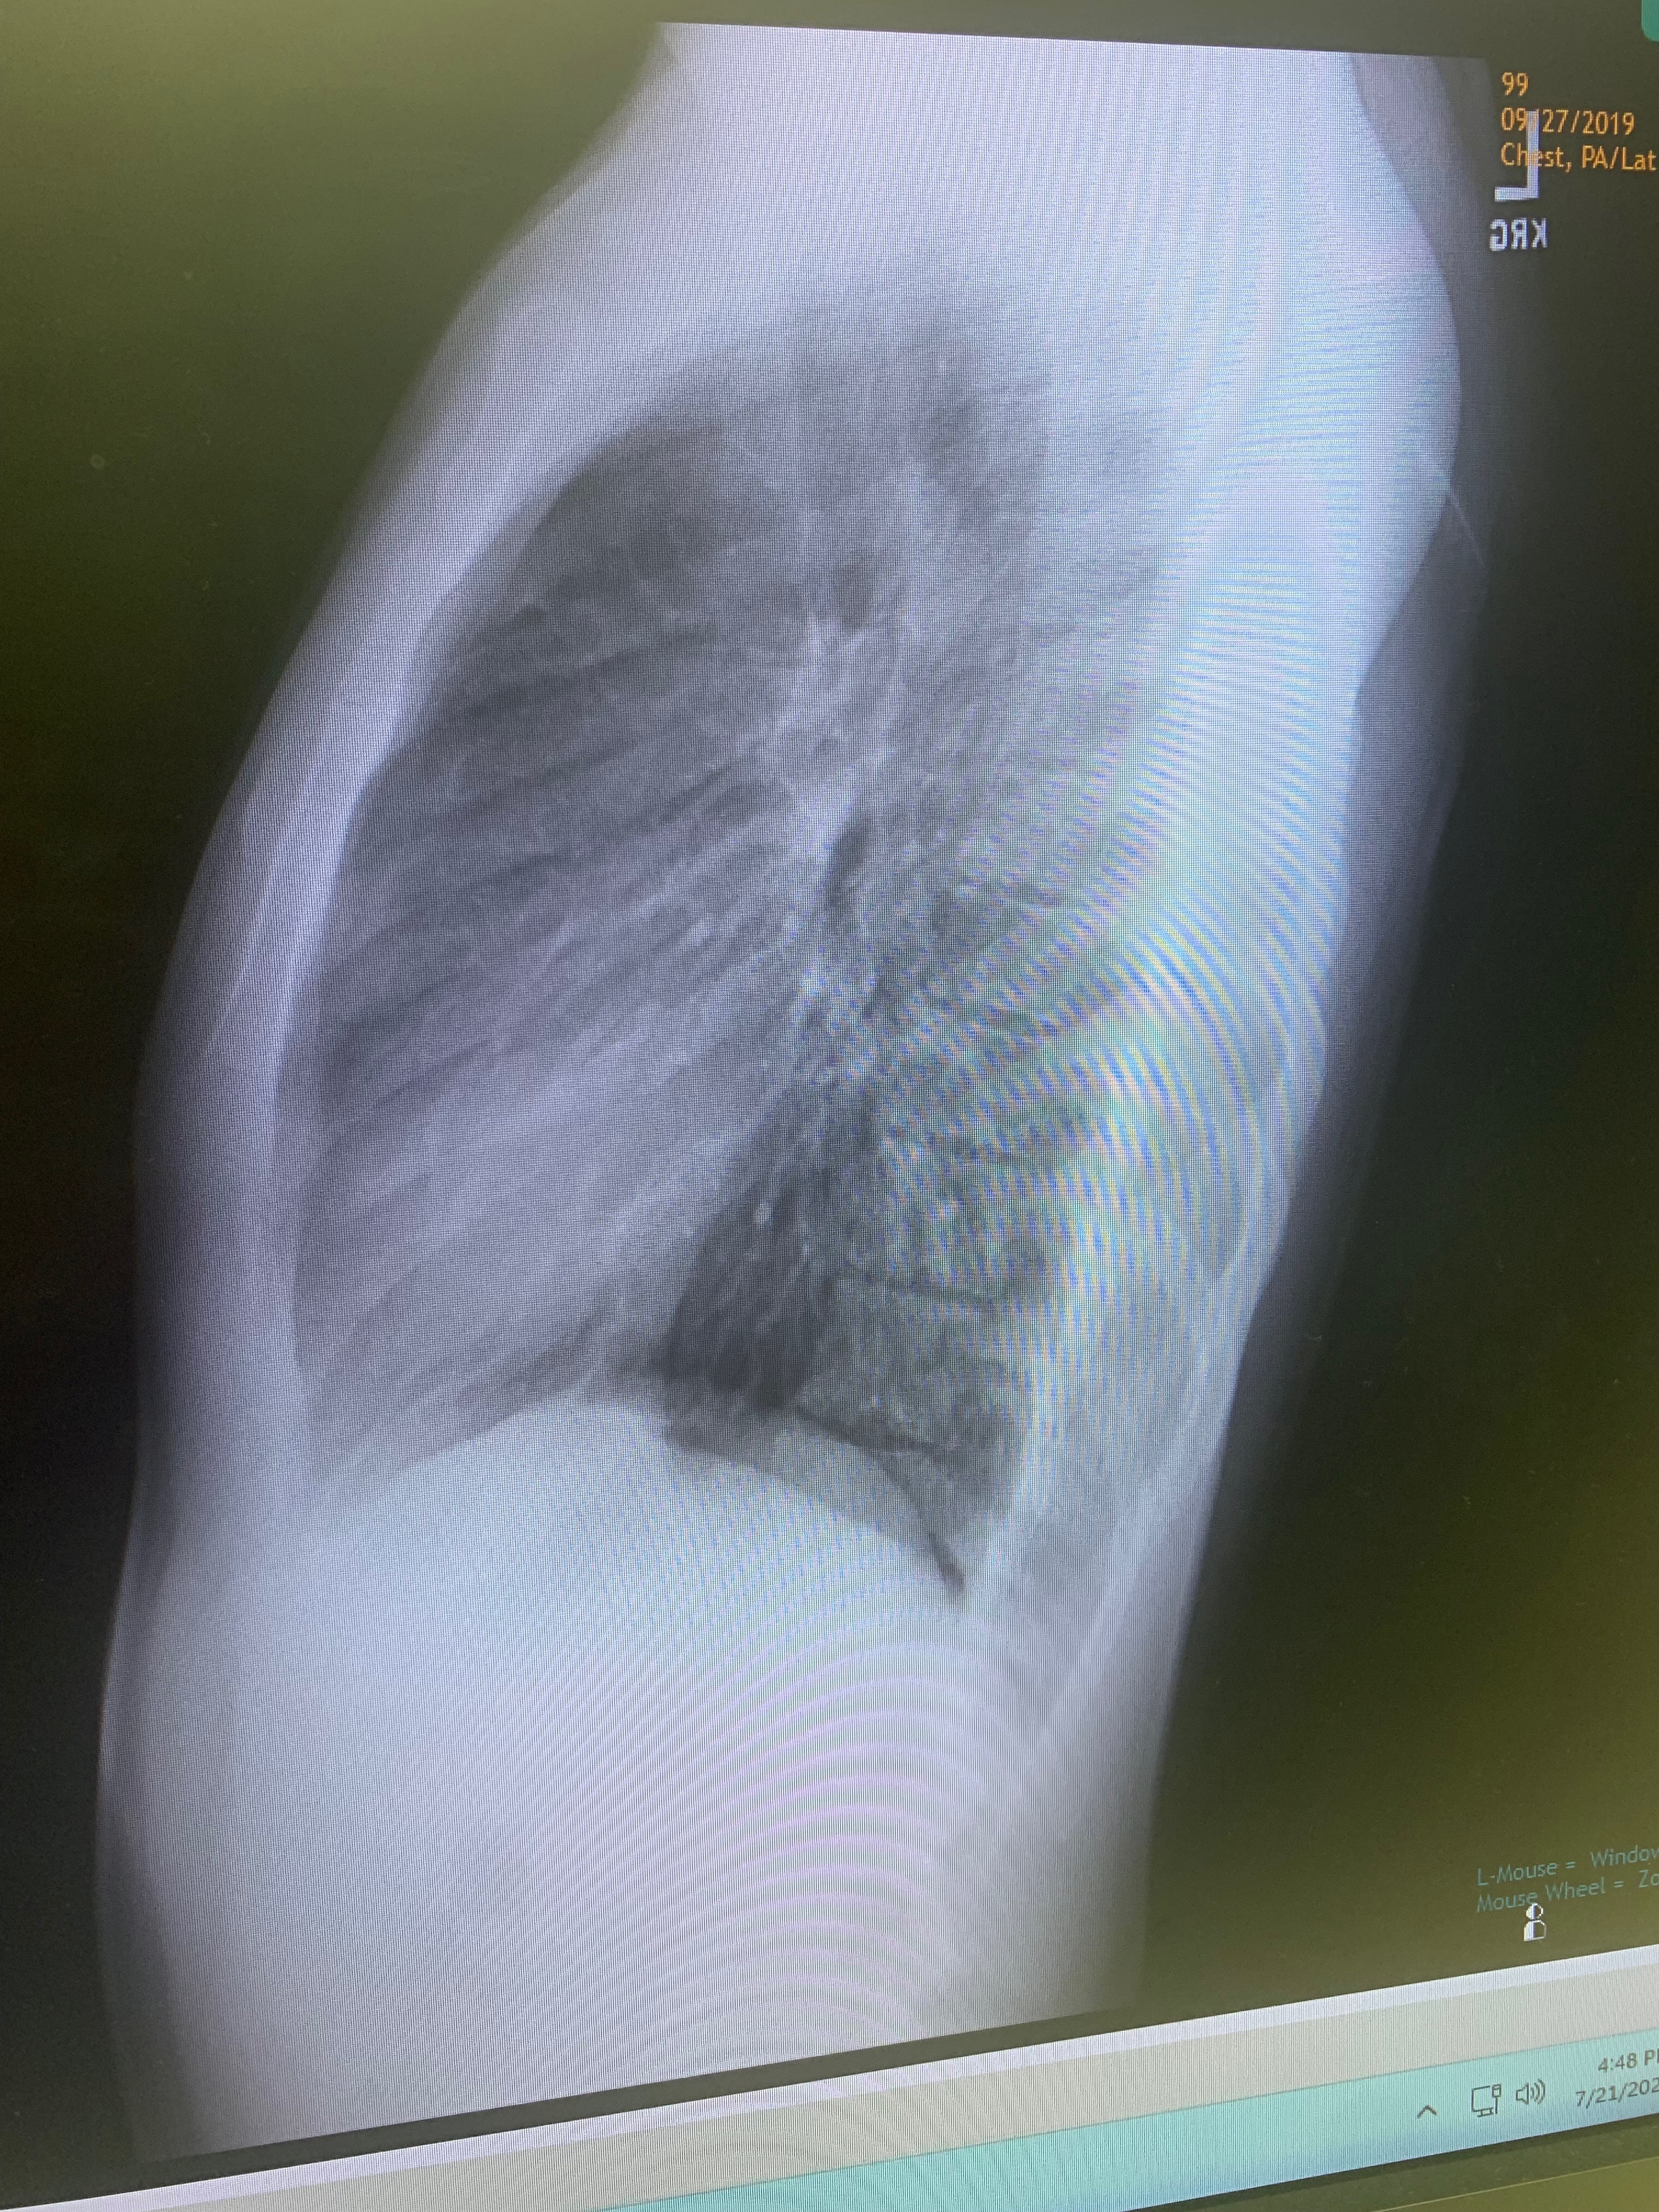

Hi, my name is Brandon. I’m 22 years old, and right now, I’m in the middle of a fight I never expected to face—I'm battling Lymphoma, a type of cancer that has changed my life in ways I couldn’t have imagined.